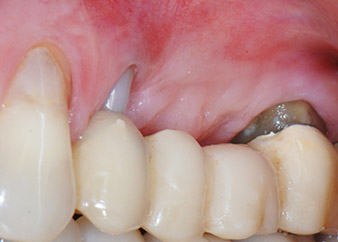

A 58-year-old female patient complained of pain and increased mobility of her bridge abutment tooth 24. Periodontal inflammation was present with pocket depths of 7 mm mesiobuccally and more than 12 mm distally, as well as third-degree furcation involvement. Moreover, the radiograph revealed an extensive periodontal lesion around the apical region of the (alio loco) endodontically pretreated tooth 24 (Fig. 1).

One month later, on the day of surgery, pain and inflammation at tooth 24 were minimal, but mobility of Miller class 2 was still present. After opening the flaps and cleaning the periapical and peri radicular infected tissue, the extent of the bone defect became obvious (Figs. 2 and 3).

At the buccal root, all vestibular and distal bone was missing. Attachment was essentially restricted to the palatal root, underlining the preliminary poor prognosis. Tooth 27 also showed a reduced horizontal attachment and a minimal apical rarefaction (cf. Fig. 1) without clinical symptoms.

Figures 17 and 18 show the clinical result two months after the surgery. Tooth 24 exhibited reduced mobility of Miller class 1, and the soft tissues were free of inflammation. Probing was avoided at this point of time to prevent reinfection and to avoid violating the epithelial attachment. A control visit was scheduled for reentry and placement of healing abutments, six months after the insertion of the implants.